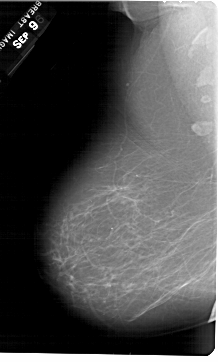

A_1354_1.RIGHT_MLO

RIGHT_MLO LINES 6721 PIXELS_PER_LINE 4246 BITS_PER_PIXEL 12 RESOLUTION 43.5 OVERLAY

FILE: A_1354_1.RIGHT_MLO.OVERLAY

TOTAL_ABNORMALITIES 1

ABNORMALITY 1

LESION_TYPE MASS SHAPE OVAL MARGINS CIRCUMSCRIBED

ASSESSMENT 4

SUBTLETY 3

PATHOLOGY BENIGN

TOTAL_OUTLINES 1